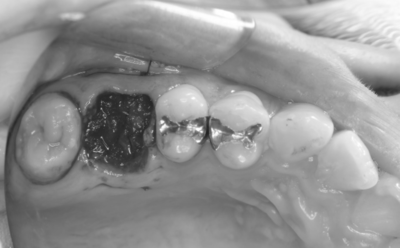

抜歯予定の歯と移植予定の歯

右上6抜歯後

右上6(青丸)を抜歯し、右下8(赤丸)を移植することを計画した。

右上の抜歯後の治癒を待つため、抜歯の1ヶ月後に移植を行うこととした。